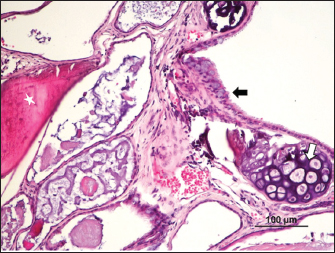

Fig. 3. Cystic mass with differentiation into stratified epithelium with accumulation of laminated keratin (*) and bone (arrow) (H&E).

The mass presented areas of epidermal differentiation with laminated keratin and sebaceous glands. Cell differentiation into digestive and respiratory epithelium, bone, cartilage, and vast areas of differentiation into nervous tissue were also present (Figs. 37). Moreover, the nervous tissue presented focal areas of ependymoma. Epithelial areas with hypercellularity, cell atypia, stromal microinvasion, hemorrhages, and necrosis were also observed. Metastatic epithelial cells were detected invading the pancreas, the small intestine serosa, and the mesenterium. Therefore, the mass was classified as a malignant teratoma with abdominal carcinomatosis.